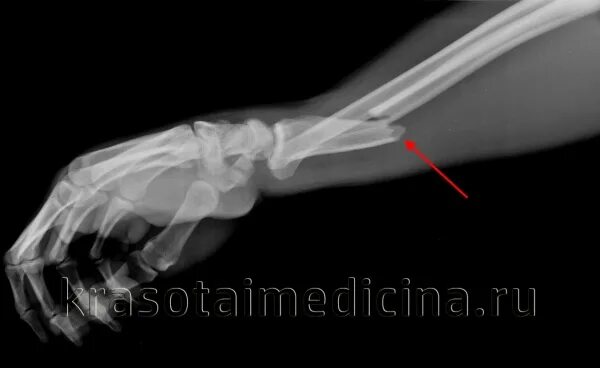

Перелом костей предплечья мкб